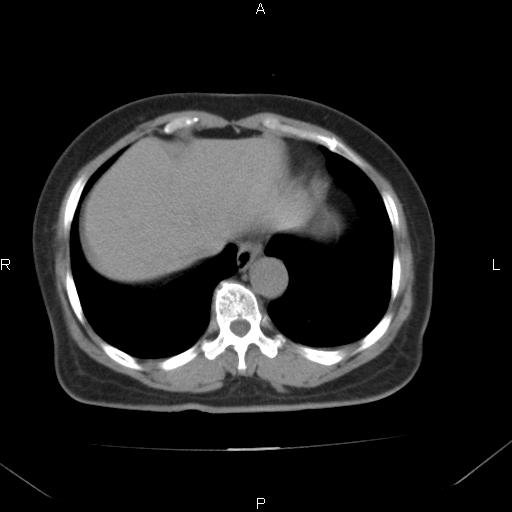

胸腺瘤

女、63Y 双眼睑下垂,早轻晚重。 胸腺瘤???

结果胸腺瘤